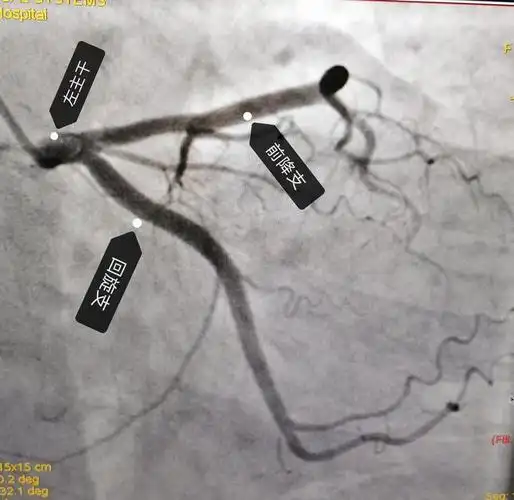

冠状动脉造影,左冠状动脉造影,左前降支狭窄.

冠状动脉造影,左冠状动脉造影

冠状动脉造影